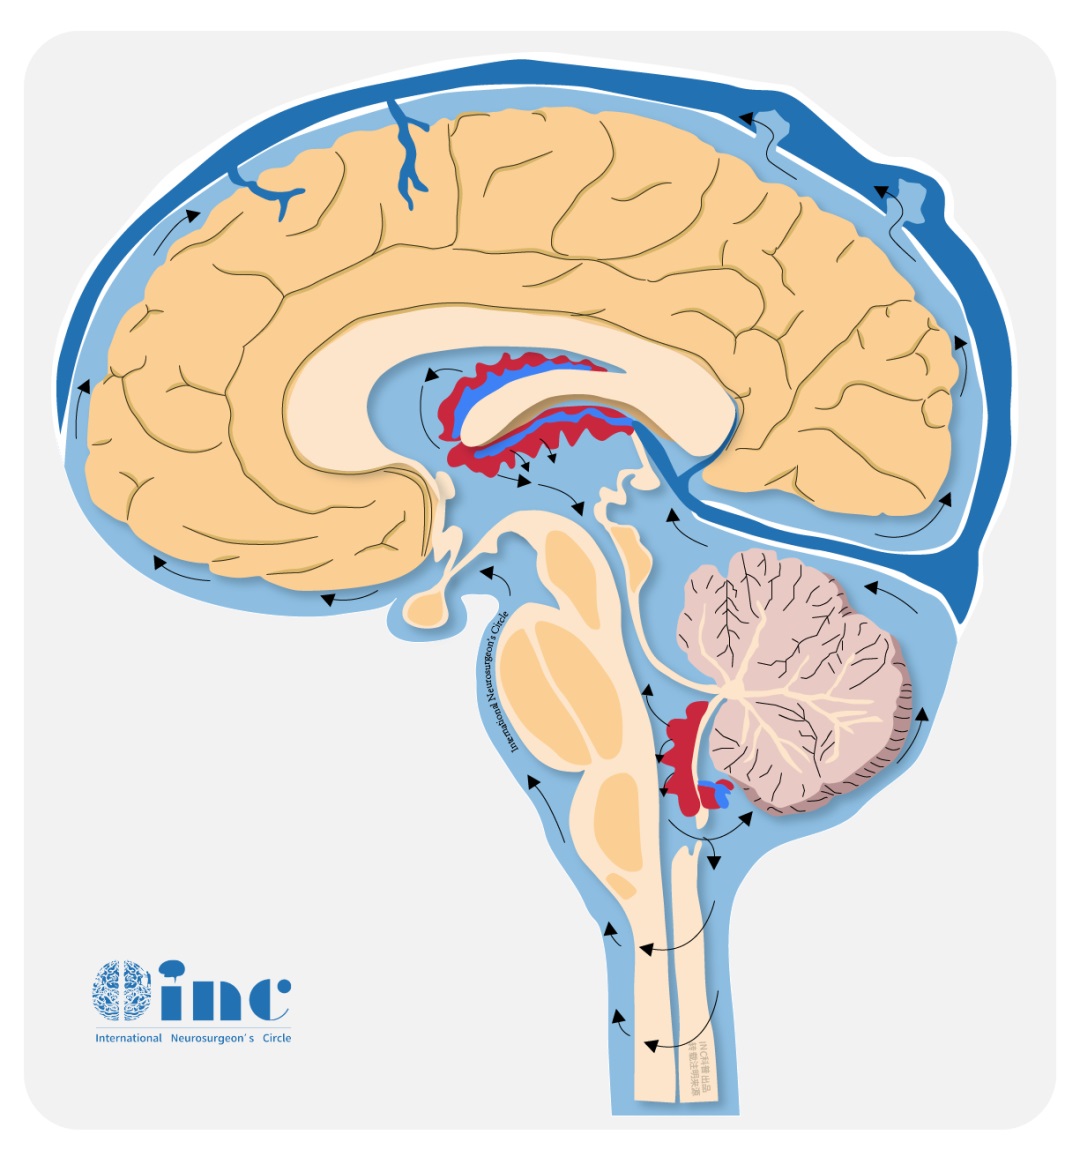

基于后颅窝内病变的活检结果,当时诊断为弥漫性软脑膜胶质神经元肿瘤(DL-GNT),弥漫性软脑膜胶质神经元肿瘤是少见的肿瘤,主要出现在儿童时期(男性偏多),大多数是4至9岁的儿童。只有在少的情况下,青少年或年轻的成年人会出现这种肿瘤。症状主要由于伴有的脑积水造成(主要是头痛),而局灶性神经功能障碍,如果存在,也可能与脊柱根的受累有关,这取决于该病变的脑膜内位置。相关的脑积水被解释为脑脊液循环受阻,这是因为曾粗的软脑膜导致中脑导水管进行性的变窄,和因为蛛网膜下腔内肿瘤细胞的聚集。软脑脊膜的曾粗和脊柱内多发结节状的病灶导致孩子的弯曲能力受限和下肢被动伸展时有阻力。

从文献中提取的一些图像说明了刚才提到的情况:增强的蛛网膜的病理性增粗,肿瘤的多个结节状定位,相关的脑积水。大脑的非强化局灶性囊性病变是由血管周围间隙的局灶性扩大造成的,也是因为脑脊液循环受阻而扩大。